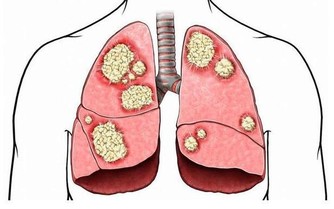

徵兆六:腦梗塞腦出血

這是糖尿病並發症中高危一種疾病,如果發現治療不及時,病人會出現暈迷,休克,隨便會出現生命危險。